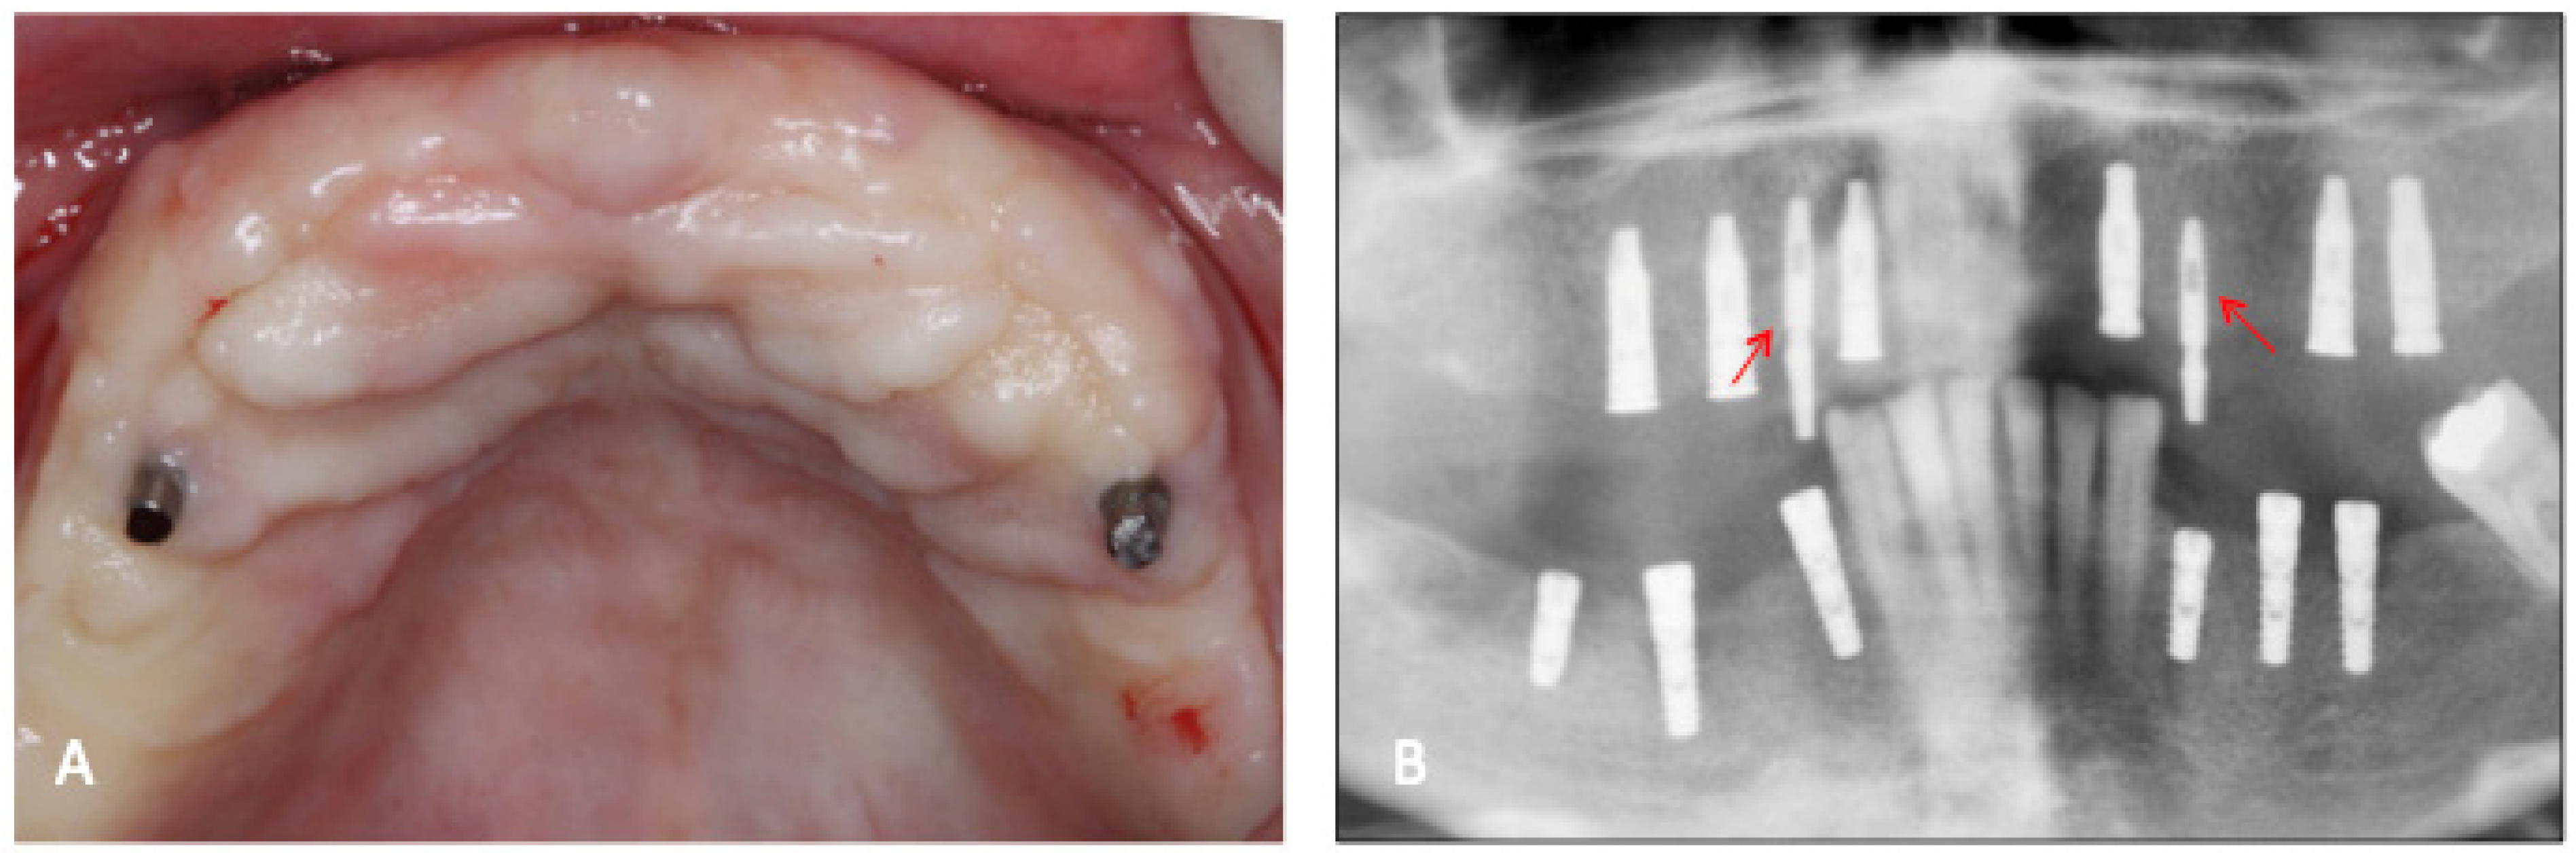

2. Materials and Methods

3. Results